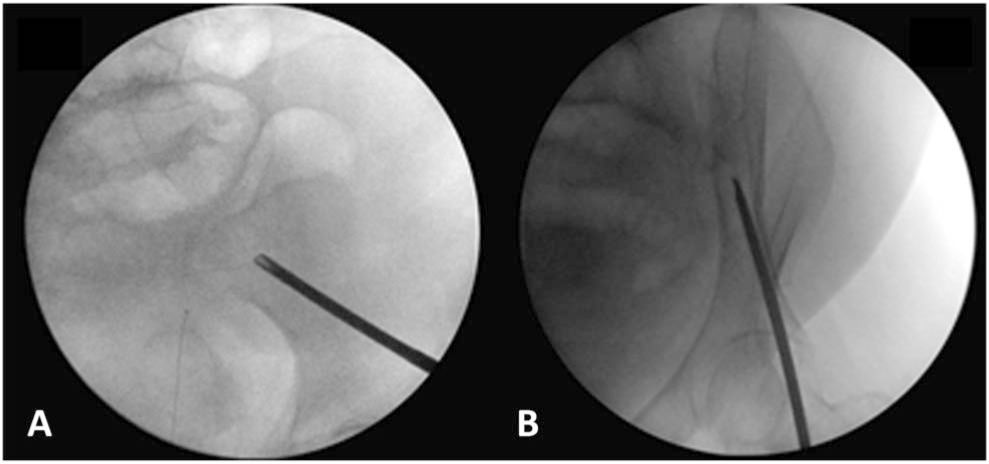

骨盆环外固定通常有2种方式:髂嵴固定和髋臼固定。通常选择2-3个5mm的半螺纹斯氏钉固定于两侧髂骨翼,然后再用连接杆将两侧连接。术中置钉注意避免损伤股外侧皮神经。Rupp等研究发现髂前上棘(ASIS)后侧2-3cm,向髂嵴延伸6-8cm的区域骨质较厚(最厚达4cm)。该位置置钉,可以减小皮质穿孔的风险。明确置钉的安全区域,能够减少透视次数,缩短手术时间。最后透视下(骨盆出口位和闭孔斜位)进一步确定置钉位置的准确性(见图1)。骨盆外固定嵴下入钉比较少见,入钉点位于ASIS的中点的内侧和髂骨内层的外侧之间,螺钉头指向髂骨结节。

图1所示。A.髂骨斜位X线片显示斯氏针位于坐骨支。B.闭孔斜位X线片显示斯氏针位于髂骨的内外板间。